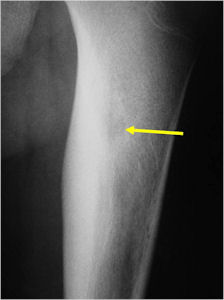

- • Scans include X-ray, CT, MRI, Bone scans. When it is very small and only a few millimeters it can be difficult to see on an Xray and MRI. The MRI usually shows extensive swelling around the tumor that can make it difficult to see the actual tumor on the MRI.

Radiographic imaging is used to help form a diagnosis. These include X-Ray, MRI, CT and Bone Scans.

An example of an osteoid osteoma is shown.